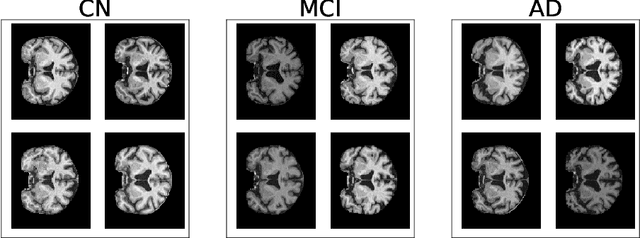

Abstract:In recent years, many papers have reported state-of-the-art performance on Alzheimer's Disease classification with MRI scans from the Alzheimer's Disease Neuroimaging Initiative (ADNI) dataset using convolutional neural networks. However, we discover that when we split that data into training and testing sets at the subject level, we are not able to obtain similar performance, bringing the validity of many of the previous studies into question. Furthermore, we point out that previous works use different subsets of the ADNI data, making comparison across similar works tricky. In this study, we present the results of three splitting methods, discuss the motivations behind their validity, and report our results using all of the available subjects.

Abstract:A plethora of deep learning models have been developed for the task of Alzheimer's disease classification from brain MRI scans. Many of these models report high performance, achieving three-class classification accuracy of up to 95%. However, it is common for these studies to draw performance comparisons between models that are trained on different subsets of a dataset or use varying imaging preprocessing techniques, making it difficult to objectively assess model performance. Furthermore, many of these works do not provide details such as hyperparameters, the specific MRI scans used, or their source code, making it difficult to replicate their experiments. To address these concerns, we present a comprehensive study of some of the deep learning methods and architectures on the full set of images available from ADNI. We find that, (1) classification using 3D models gives an improvement of 1% in our setup, at the cost of significantly longer training time and more computation power, (2) with our dataset, pre-training yields minimal ($<0.5\%$) improvement in model performance, (3) most popular convolutional neural network models yield similar performance when compared to each other. Lastly, we briefly compare the effects of two image preprocessing programs: FreeSurfer and Clinica, and find that the spatially normalized and segmented outputs from Clinica increased the accuracy of model prediction from 63% to 89% when compared to FreeSurfer images.